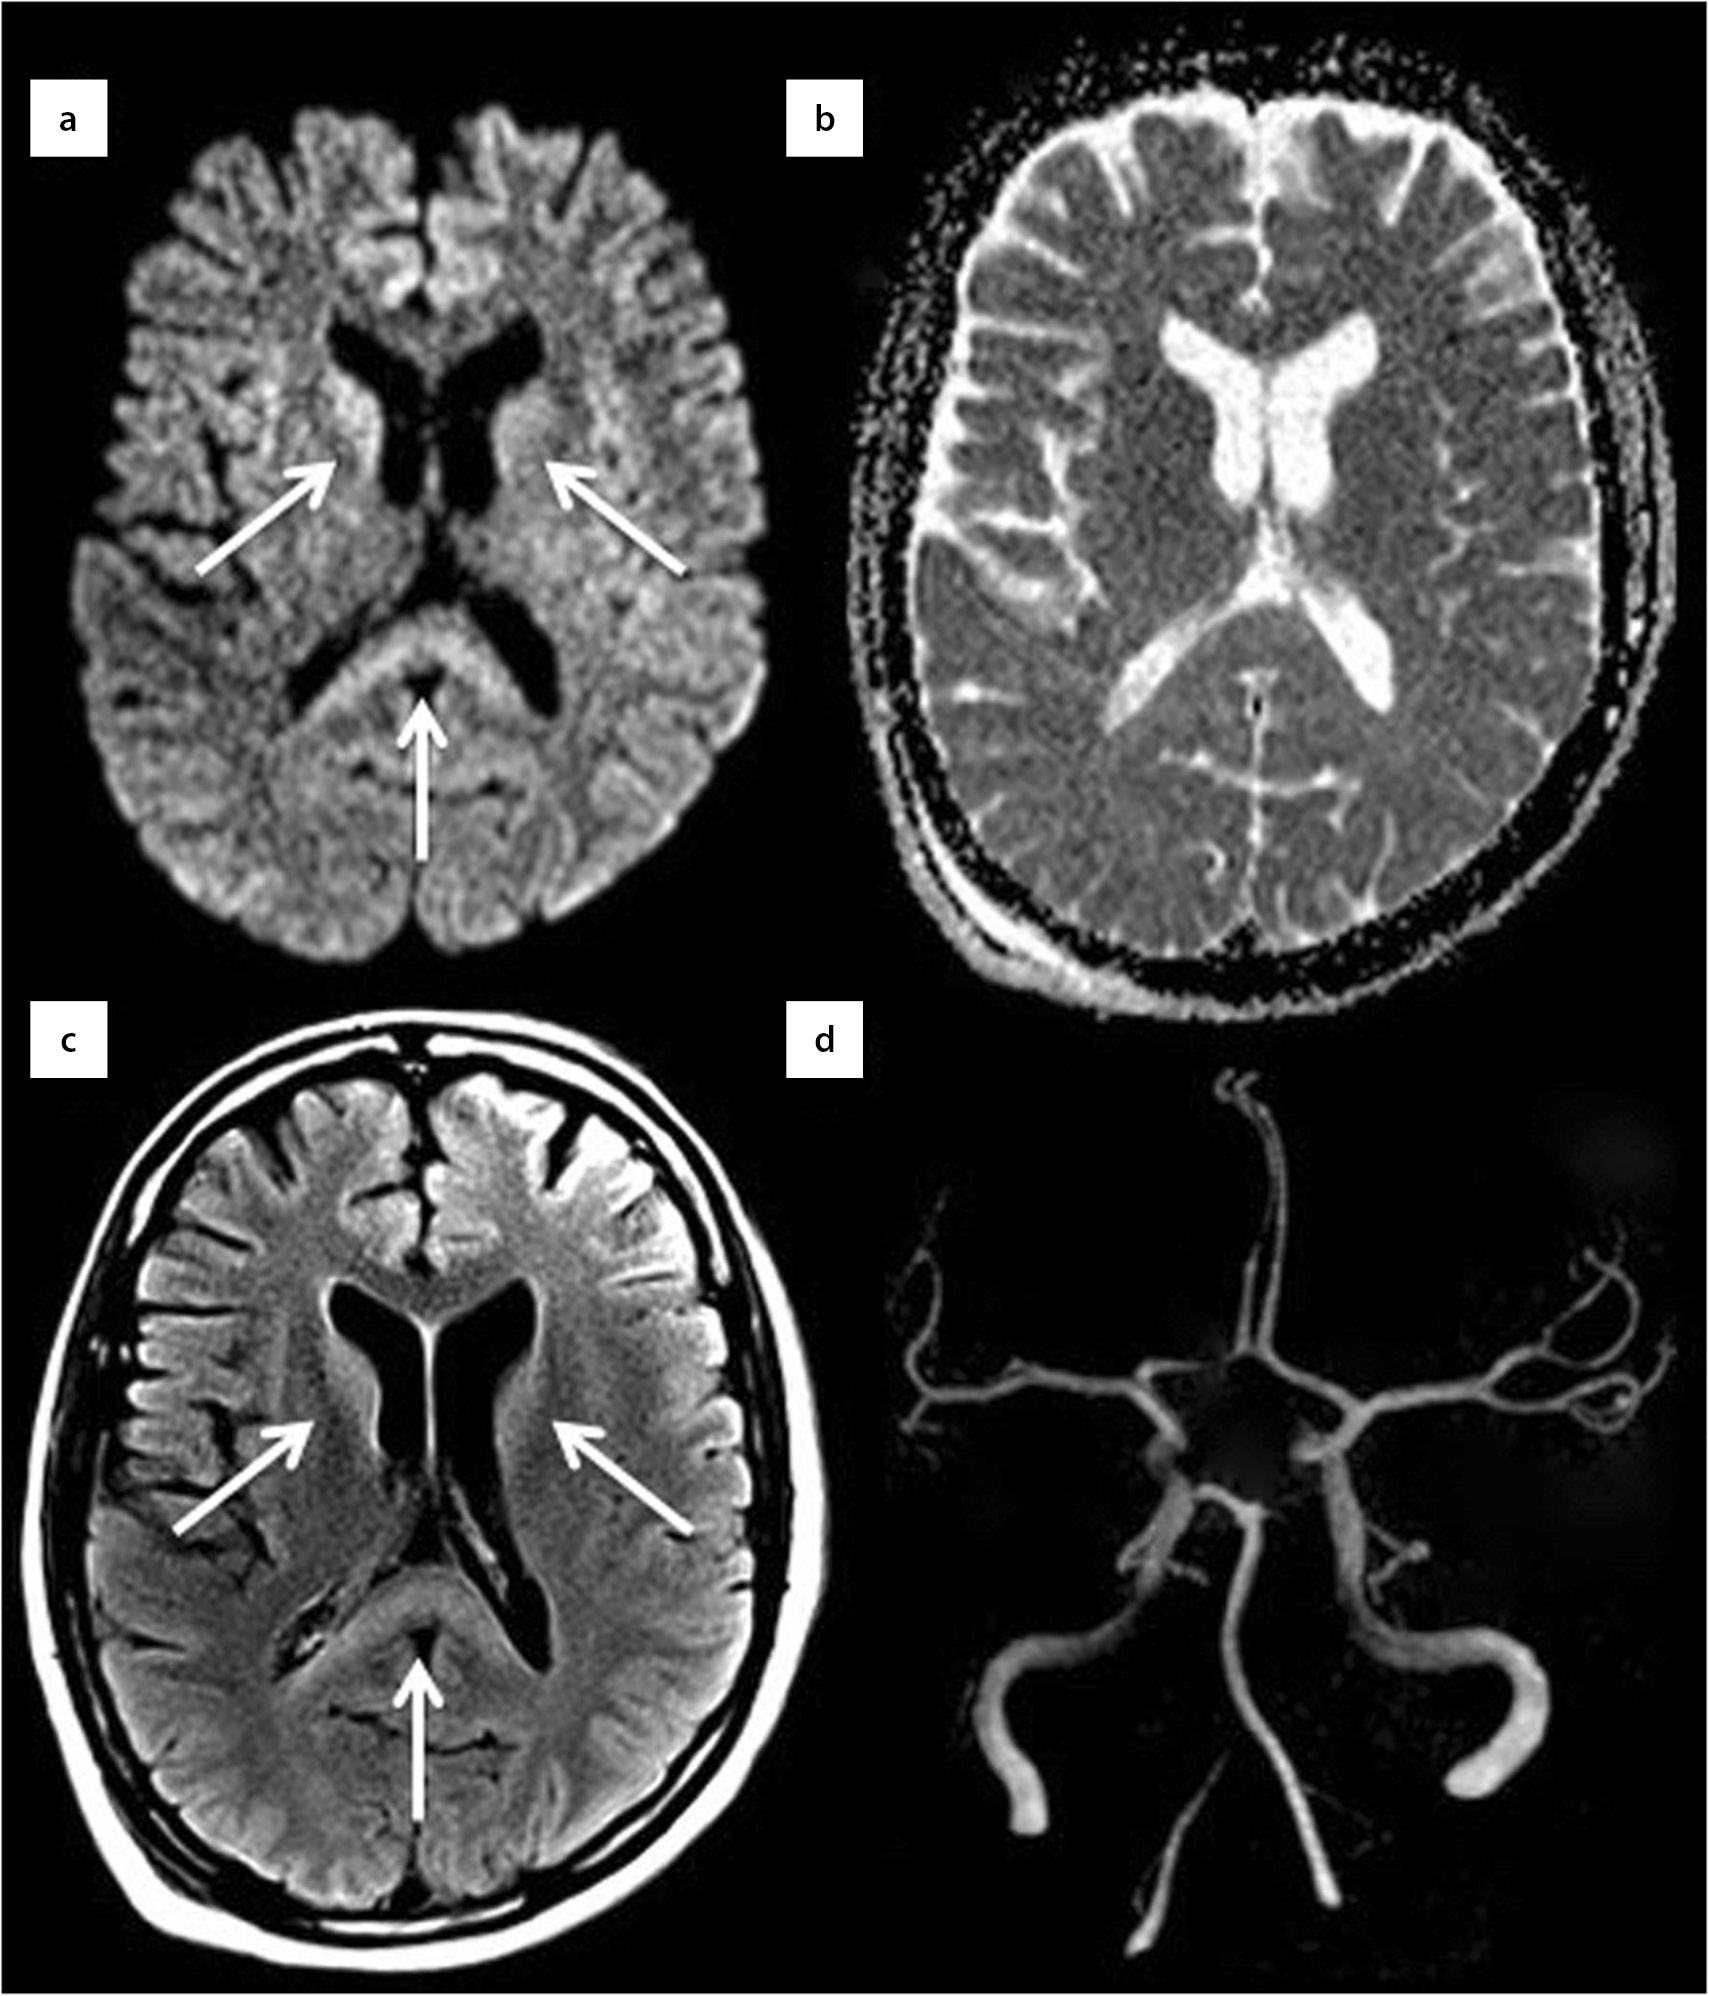

2. Изменения МР-сигнала включают гиперинтенсивность на диффузионно-взвешенных режимах исследования и в режиме FLAIR, небольшую гиперинтенсивность на T2-взвешенных изображениях и небольшую гипоинтенсивность на T1-взвешенных изображениях. Диффузионно-взвешенное изображение (ДВИ) играет важную роль в ранней диагностике ГЭ. (рис. 2).

Рисунок 2. Данные МРТ. Тяжелая гипогликемия у 42-летней женщины. Визуализируется гиперинтенсивность в базальных ганглиях и валике мозолистого тела (стрелки a, c) без признаков острого ишемического повреждения в режиме ДВИ (b) и значимых изменений интракраниальных артерий (МР-ангиография) (d). Приводится по Adam G и соавт. [49].